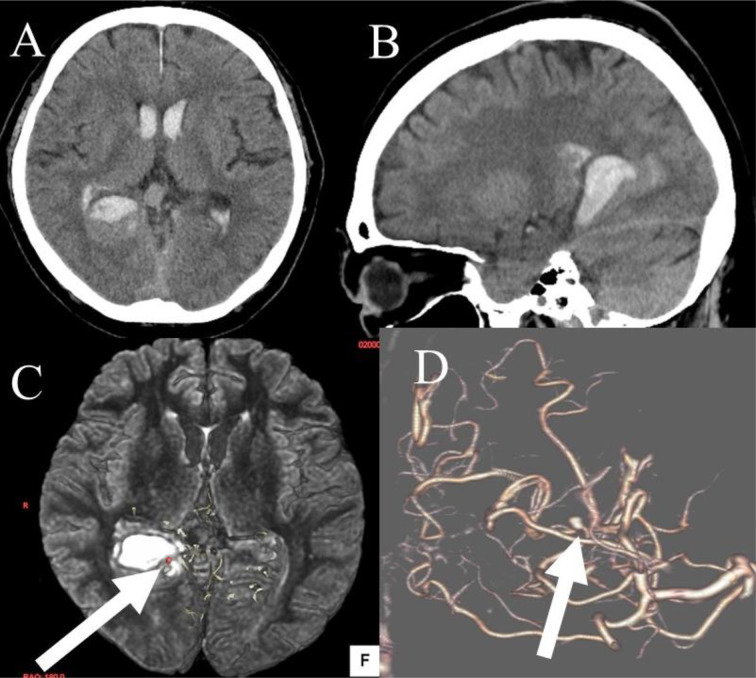

Objective: This report describes a rare case of a dural arteriovenous fistula of the falcine sinus associated with a flow-related aneurysm.

Patient and methods: A 68-year-old man presented with severe headache secondary to an intracranial hemorrhage. The bleeding was caused by a dural arteriovenous fistula (dAVF) of the falcine sinus with a flow-related aneurysm of the dural branch of the right posterior cerebral artery.

Results: Trans arterial obliteration of the aneurysm and its feeder using glue and trans venous embolization of the draining portions using a coil were successfully performed.

Conclusion: The unusual coexistence of a flow-related aneurysm on the feeder of the dAVF resulted in a unique hemorrhage.